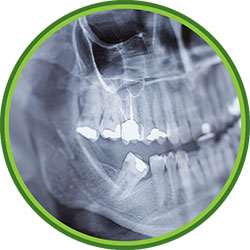

Dental Assessment

Before we do any work, we need to do a diagnosis. The majority of our patients do a Comprehensive Oral Examination so that they can have their full mouth assessed. The latter option is a specific exam, which costs about the same and is only focused on one specific tooth/ area, but is much quicker than the COE.